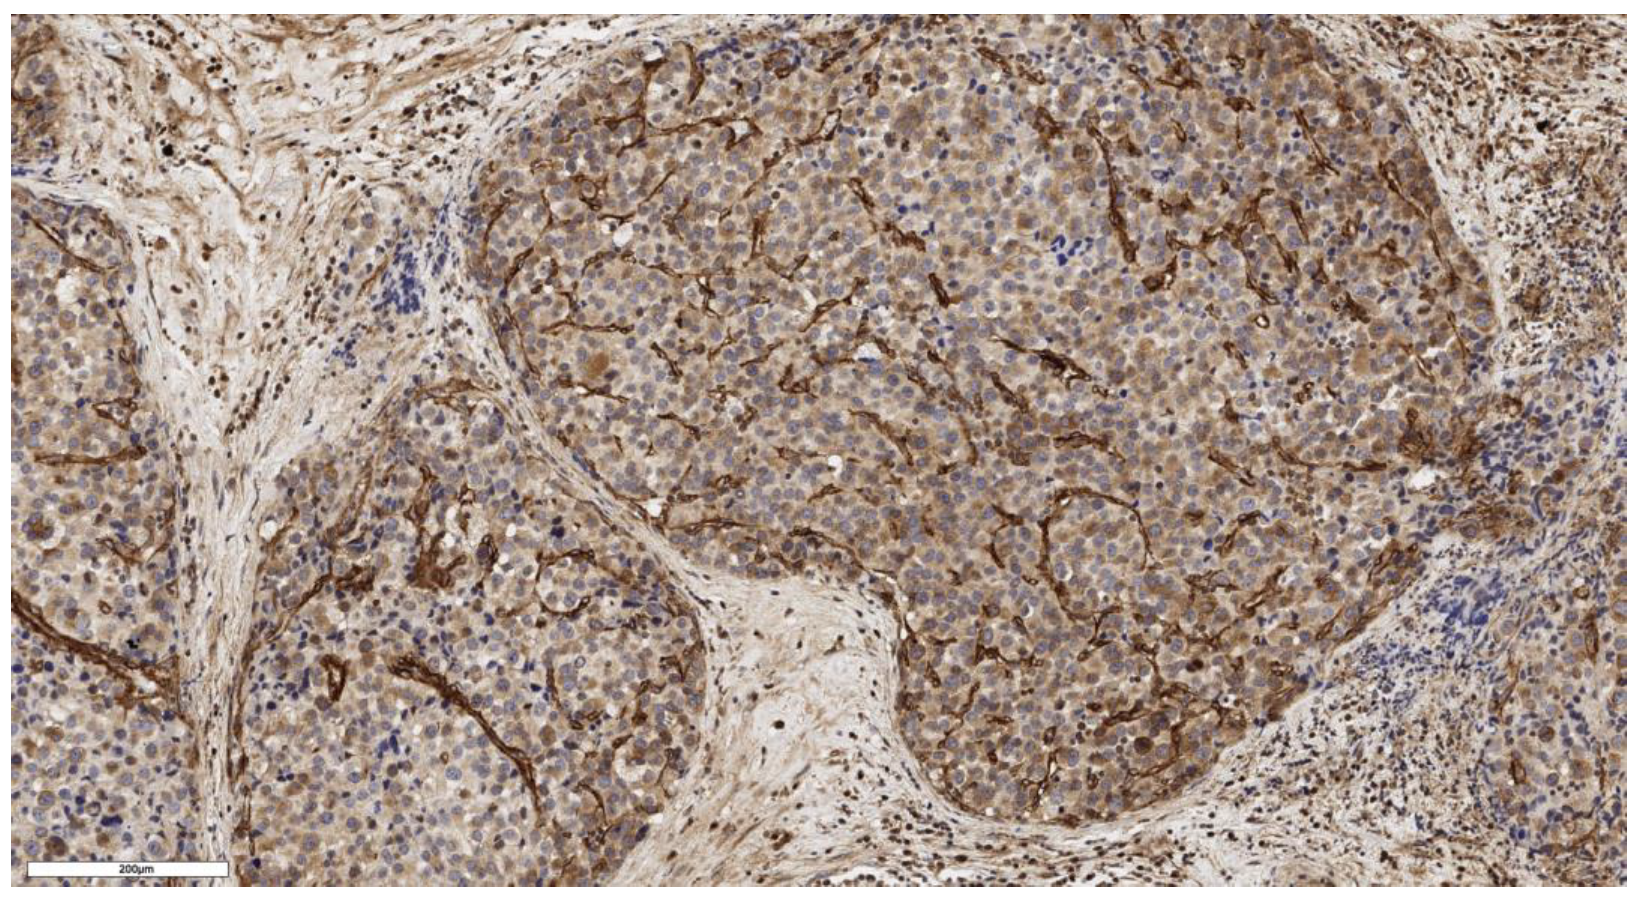

3.1. Analysis of CD90 Marker Expression

3.2. Analysis of LGR5 Marker Expression

3.4. Analysis of Stem Marker Expression in Normal Adrenal Tissue